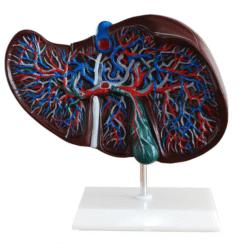

ATL-12 MALE MUSCLES FIGURE 2 PARTS

The model is an anatomically accurate representation of the human anatomy, complete with superficial and deep musculature, the digestive system, lymphatic system, respiratory system, urinary system, circulatory system, endocrine system, and nervous system. Our model has removable organs and dissectible features for a complete educational experience.

Classification:

Skeleton Models(human bone, muscle, etc.)